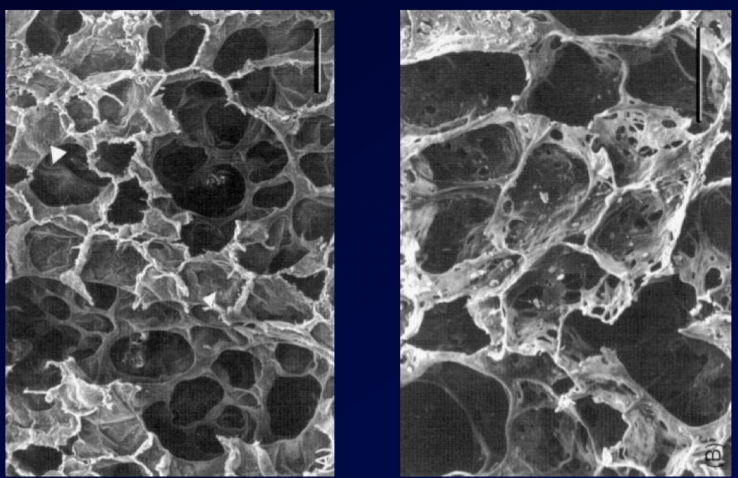

This pathology represents the ______ portion of COPD

Which side is normal? Which is COPD?

This pathology represents the emphysema portion of COPD

Left is normal, right is emphysema